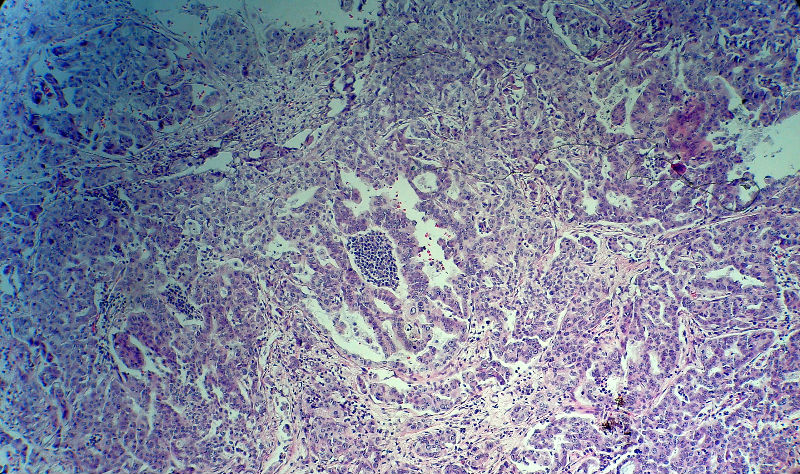

肿瘤呈巢片状分布,细胞大小相对一致,胞浆丰富,胞核呈细颗粒状,可见小核仁,血管较丰富,考虑神经内分泌肿瘤,加做免疫组化(Ki67、Syn、NSE、CgA、CD56)分级。

肠系膜淋巴结

神经内分泌肿瘤,加做免疫组化(CKp、Ki67、Syn、NSE、CgA、CD56)分级。